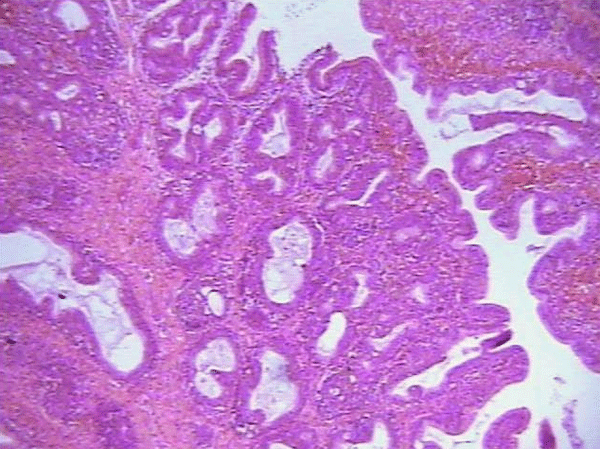

Enfermedad de Gumboro: depleción linfoide y lesiones atróficas, pueden ser inducidas por las vacunas? - Image 8

Imagen No 8 Cortes (Coloreados con Hematoxilina Eosina, 10X y 40X respectivamente) de bolsa de Fabricio de un pollo de 25 días de edad. Obsérvese que la afección no es uniforme en los folículos que componen la folia, encontrándose unos más afectados que otros. La fotografía de la derecha contiene lo que se describe como una cavidad quística, esto permite un diagnóstico de enfermedad de Gumboro.